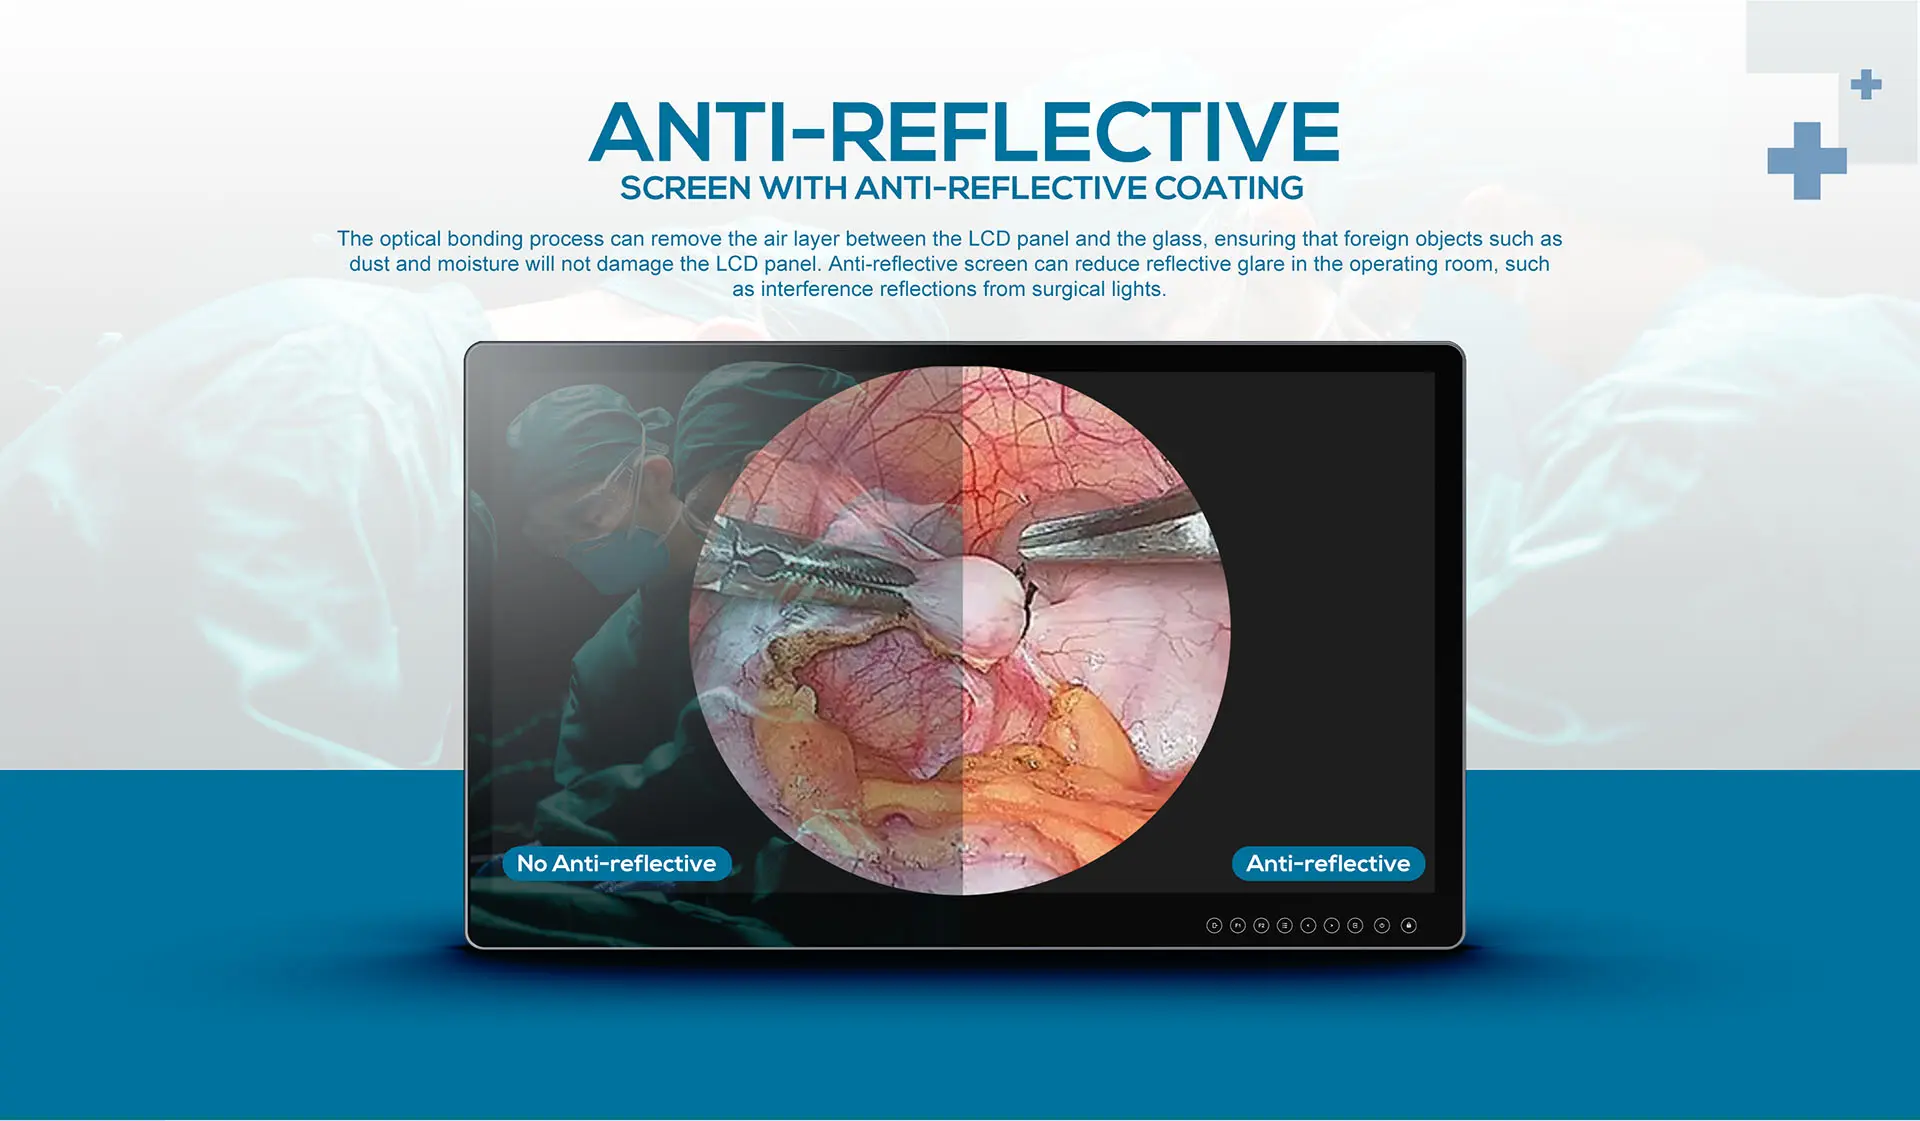

- Optical bonding process, anti-glare glass panel

- Anti-reflective, anti-fingerprint coating